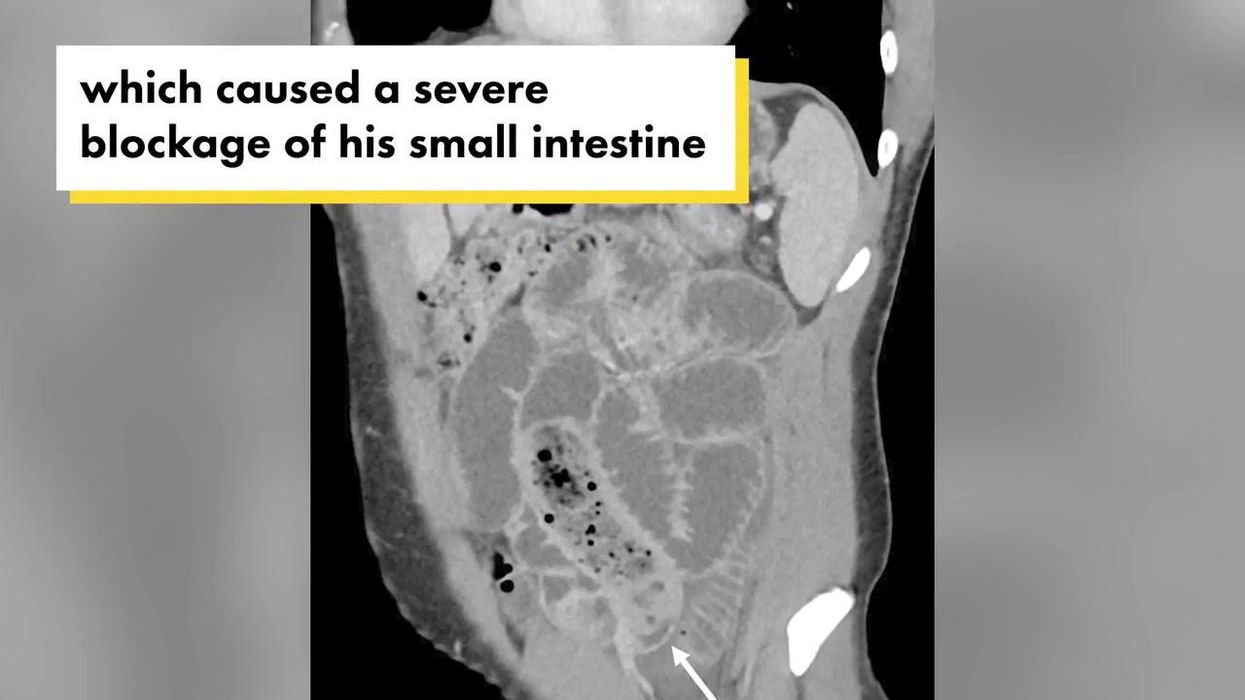

The 34-year-old man turned up at his local A&E department suffering from stomach pain, nausea and vomiting which he said had begun seven hours earlier.

He was suffering so much that he couldn’t eat or drink, he said, and hadn’t been to the toilet since the day before.

He’d eaten a banana stuffed in a condom.

The “otherwise healthy” man admitted to having swallowed the double-sheathed banana during a “hormonal rage” 24 hours earlier.

Fortunately, surgeons were able to remove the ill-advised snack from his small bowel and he went on to make a full recovery.